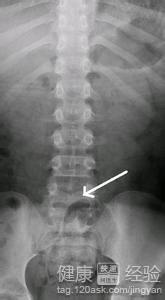

1隱形脊柱裂的病症通常會造成脊椎錯位或者脊椎接位不正常,這樣會使泌尿系統紊亂,造成孩子的心理自己生理不正常,但是家長的安慰是非常重要的,保持孩子良好的心態更加有利於孩子的治療,如果能不做手術的話盡量不要做。

2孩子在生長發育期由於缺鈣或者鈣質吸收不進去,或者在孕婦懷孕時自己缺少鈣造成腰間的骨頭發育不好,然後脊背出現了小裂縫,這是常見的一種現象,這種情況一般患者隨著年齡增長逐漸就自愈了,是不需要去治療的,

3雖然是不需要治療,但是尿床症狀一定要重視起來,畢竟有隱性脊柱裂的患者不是都尿床的,所以,治愈尿床症狀是首要問題,可以早點去醫院檢查,如果有這樣症狀,就應早點治療,如果是這樣原因,患者應注意飲食還有自身的心情。